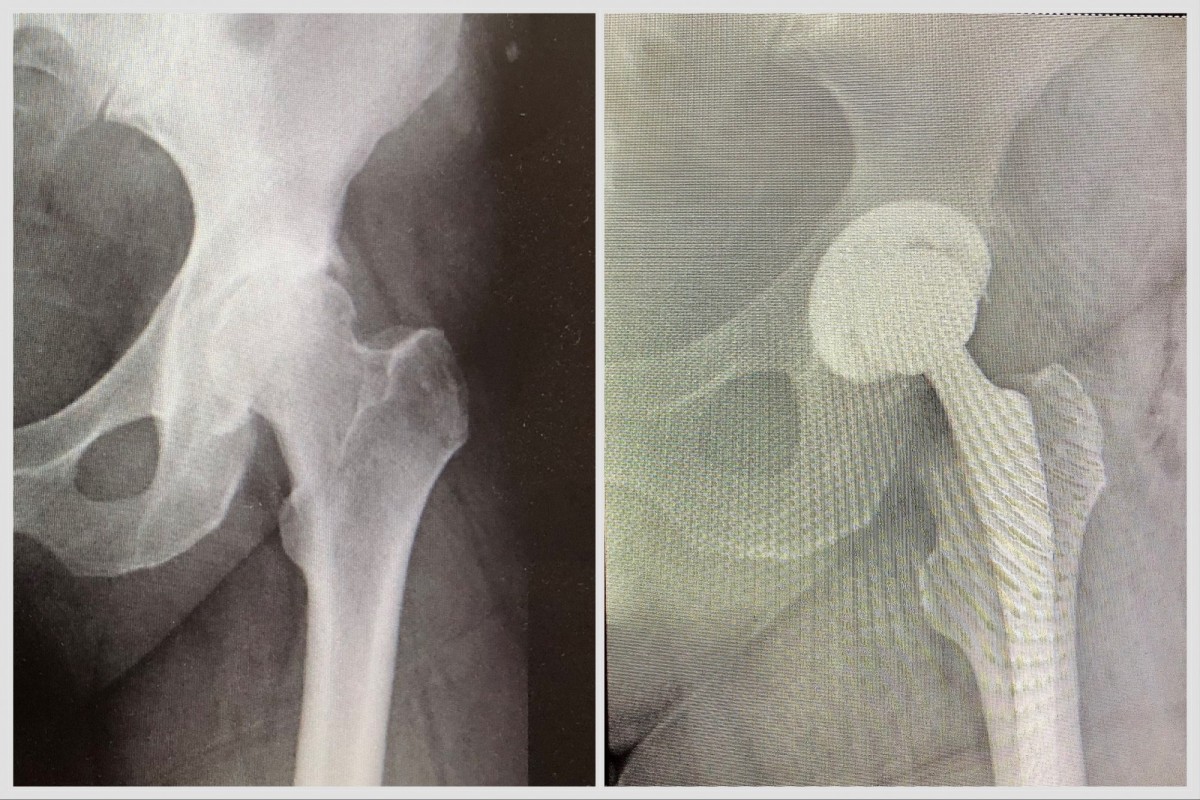

Врачи Видновской КБ спасли 51-летнюю пациентку с третьей стадией ожирения, у которой было дегенеративно-дистрофическое заболевание бедра. На момент операции вес женщины составлял 125 килограммов. Как рассказал заведующий травматологическим отделением Ибрагим Абакаров, в больницу пациентка была доставлена с диагнозом «Коксартроз тазобедренного сустава левой ноги». На протяжении нескольких лет ее мучили нестерпимые боли, движения в суставе были ограничены. Для снижения нагрузки на сустав ей было рекомендовано снижение веса, для чего была необходима двигательная активность. Однако из-за выраженного болевого синдрома женщина не могла выполнять рекомендации врачей. Между тем, прогрессирование болезни грозило атрофией мышц бедра и укорочением конечности.

Видновские врачи приняли решение провести оперативное вмешательство, несмотря на сопутствующие диагнозы – ожирение, гипертонию, сердечную патологию и диабет. Травматологи выполнили сложную хирургическую операцию – заменили пораженный болезнью бедренный сустав искусственным. Благодаря малоинвазивному методу вмешательства кровопотеря была минимальной, так что уже на другой день пациентка была активизирована.

– Безусловно, существовал риск оперативного вмешательства для данной пациентки, и даже технически было сложно проводить оперативное вмешательство из-за большого количества жировых тканей. Доступ к пораженному суставу был затруднен. Но так как женщина трудоспособного возраста, ее необходимо было вернуть к нормальной жизни, – рассказал Ибрагим Абакаров.